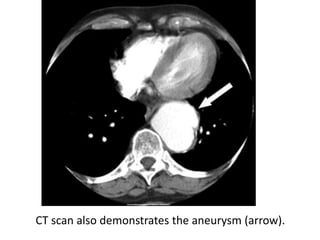

Posteroanterior chest radiograph shows lateral displacement of the lateral

margin of the descending thoracic aorta due to an aortic aneurysm

(arrowheads).

CT scan also demonstrates the aneurysm (arrow).